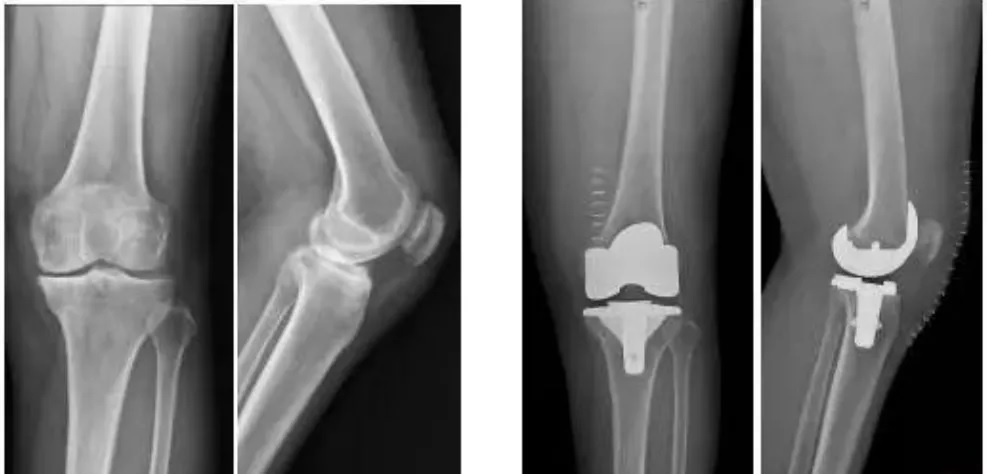

9月30日,四川大學華西醫院骨科的周宗科教授團隊成功為(wei) 患有膝關(guan) 節骨關(guan) 節炎的吳婆婆植入了3D打印分區骨小梁生物型膝關(guan) 節假體(ti) 。飽受膝關(guan) 節疼痛折磨多年的她,在接受手術20多天後,恢複了正常的行走能力。

這種新型假體(ti) 與(yu) 傳(chuan) 統骨水泥假體(ti) 相比,其通過假體(ti) —骨界麵緊密接觸,促使骨組織長入假體(ti) ,提高假體(ti) 與(yu) 髓腔的結合強度,從(cong) 而達到假體(ti) 的長期穩定。使用生物型人工膝關(guan) 節,可保存患者骨量,同時避免或降低了骨水泥所導致的毒副作用。

全球首款3D打印,分區骨小梁生物型膝關(guan) 節假體(ti)

本次植入的生物型膝關(guan) 節假體(ti) 在術中無需使用骨水泥,通過機械方式進行固定,即假體(ti) 與(yu) 骨組織的緊密結合,獲得假體(ti) 的初始穩定性,遠期骨組織長入假體(ti) 表麵的微孔內(nei) 部,實現由機械固定向生物內(nei) 鎖固定的轉化,最終經過骨整合作用獲得良好固定,預期能夠獲得更長的假體(ti) 壽命。

此外,生物型膝關(guan) 節假體(ti) 避免了骨水泥相關(guan) 並發症的發生,縮短了手術時間,最大程度保留了骨組織。因而減輕了患者術後疼痛,降低了圍術期並發症發生率,有利於(yu) 患者術後快速康複。

周宗科教授介紹說,該款3D打印分區骨小梁生物型膝關(guan) 節假體(ti) 有三個(ge) 亮點,一是脛骨平台假體(ti) 采用了3D打印骨小梁分區技術,三分區設計使宿主骨均勻骨長入,避免因應力分布不均而造成平台假體(ti) 鬆動等問題;二是所用股骨髁假體(ti) 表麵為(wei) 真空等離子噴塗純鈦塗層,其粗糙的接觸麵增加了骨誘導的能力,具有優(you) 異的即刻穩定和長期穩定性;三是所用平台墊為(wei) 添加維生素E的高交聯超高分子量聚乙烯材質,具有優(you) 異的耐磨性能。